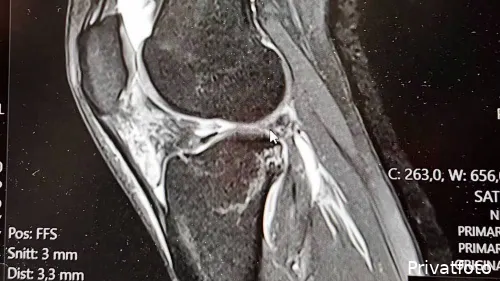

Skaden viste sig at være blandt de mest alvorlige, man kan få som skihopper.

Korsbånd, sidebånd og menisk var ødelagt, og samtidig var albuen gået af led.